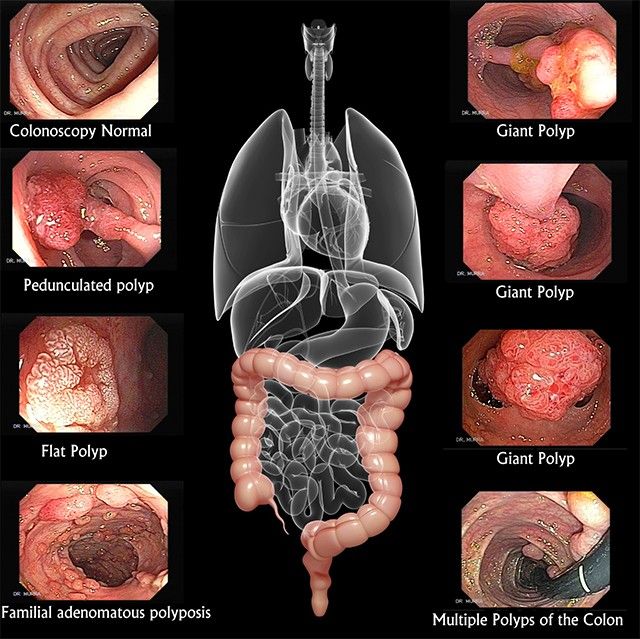

“Konsideroj që kafshët shtëpiake mund të jenë shkaktarët direkt tëkancerit të zorrës së trashë tek njerëzit. Kemi të dhëna eksperimentale që e konfirmojnë këtë tezë. Mirëpo, këtë tashmë duhet ta vërtetojmë”, ka theksuar Hausen, transmeton Telegrafi.

Edhe shkencëtarët e tjerë më herët kanë tërhequr vërejtjen që përdormi imishit të kuq(mishit të gjedhit, të viçit, të kalit, të deles dhe të derrit) rrit rrezikun e sëmurjes nga kanceri kolorektal. Mirëpo, Hausen konstaton që rreziku vjen vetëm nga mishi i gjedhit, por edhe nga qumështi i lopëve, edhe pse kjo nuk duket edhe aq e pabesueshme!

Ai gjithashtu tregon që niveli i sëmundjeve kolorektale nga kanceri është rritur shumë pas Luftës së Dytë Botërore, transmeton Telegrafi. Ai është i bindur që kjo në mënyrën më të drejtpërdrejtë është e lidhur me atë që në këto shtete është bërë i popullarizuar mishi i importuar i gjedhit.